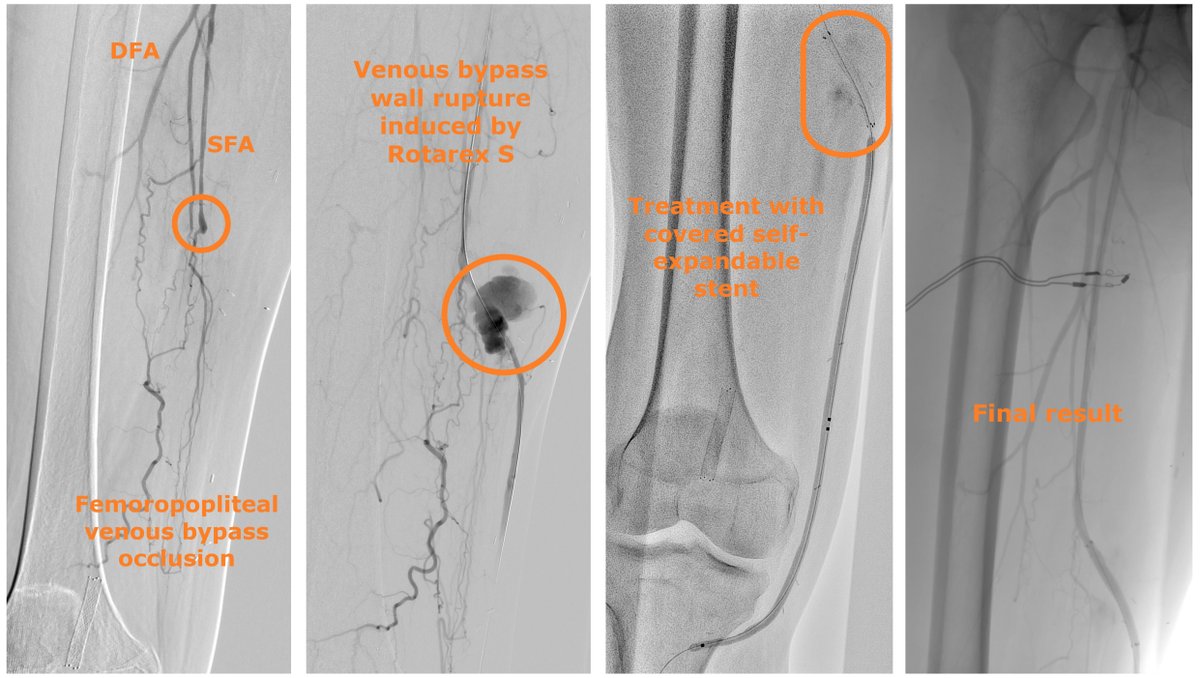

Treatment of Arterial Wall Rupture Induced by a Rotational Atherothrombectomy Device The authors report 2 cases of vessel preparation where the Rotarex S Rotational Excisional Atherectomy System (BD) induced arterial wall ruptures. hubs.ly/Q03QhCcF0

CLIjournal's tweet image. Treatment of Arterial Wall Rupture Induced by a Rotational Atherothrombectomy Device

The authors report 2 cases of vessel preparation where the Rotarex S Rotational Excisional Atherectomy System (BD) induced arterial wall ruptures.

Treatment of Arterial Wall Rupture Induced by a Rotational Atherothrombectomy Device In this Case Report, the authors report 2 cases of vessel preparation where the RotarexTM S Rotational Excisional Atherectomy System (BD) induced arterial wall ruptures. hubs.ly/Q03LpJ640

In this Case Report, the authors report 2 cases of vessel preparation where the RotarexTM S Rotational Excisional Atherectomy System (BD) induced arterial wall ruptures.